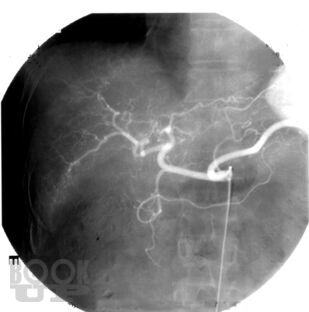

В монографии проанализированы данные литературы и собственные результаты лечения более 700 больных (1983- 2001) первичным и метастатическим раком печени. Дан обзор наиболее часто применяемых рентгеноэндоваскулярных вмешательств. В случае нерезектабельного поражения внутрисосудистая терапия включает регионарную химиоинфузию, эмболизацию, химиоэмболизацию печеночной артерии и воротной вены. Оценены возможности указанных рентгеноэндоваскулярных вмешательств, а также предоперационной механической эмболизации воротной вены при резектабельных опухолях. Рассмотрена роль адъювантной локорегионарной терапии после выполнения резекции печени. Сделано заключение о том, что рентгеноэндоваскулярные вмешательства играют важную роль в лечении злокачественных опухолей печени. Комбинированный подход к лечению злокачественных новообразований печени позволяет расширить возможности оказания помощи больным и добиться улучшения отдаленных результатов.